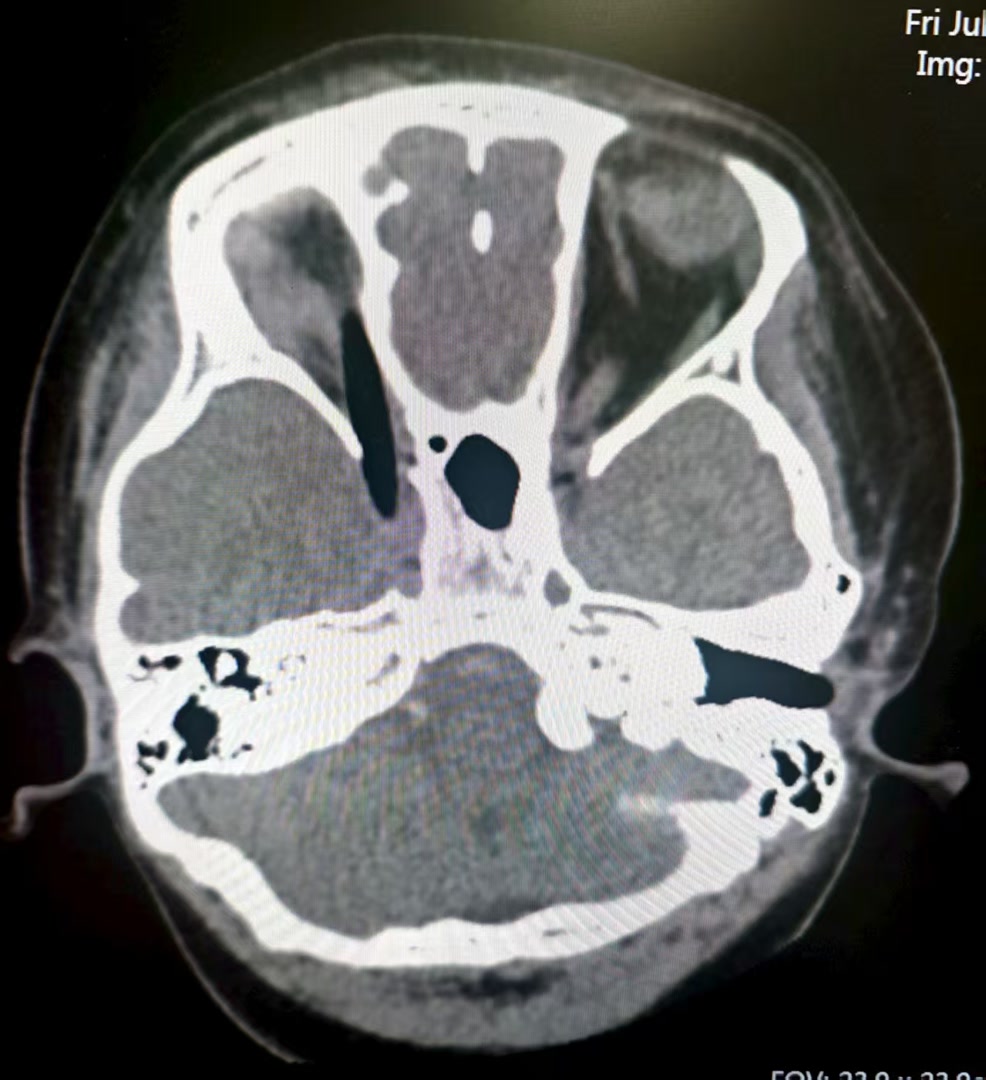

近日,小悦悦在画室爬楼梯时不慎跌倒,手中画笔自右眼眶刺入颅内。转诊至同仁医院时,患儿右眼无光感且生命体征微弱。急诊检查显示,画笔尖端逼近颅内的海绵窦,异物与血管壁最小间隙仅1.3毫米,直接拔除可能引发大出血或神经损伤。

同仁医院神经外科主任康军立即协调神经外科、眼科、麻醉科、急诊科开展多学科会诊。经综合评估,团队决定在实时脑血管造影和术中CT辅助下实施异物拔除术。手术中,医生张宝瑞通过全脑血管造影确认画笔与颅内血管神经紧密纠缠;医生孙博文凭借对颅底解剖的深刻理解,在无损伤前提下将深嵌颅内的画笔完整、平稳地移出。术后即刻二次造影及术中CT同步验证:颅内无血管渗漏,无迟发性出血。